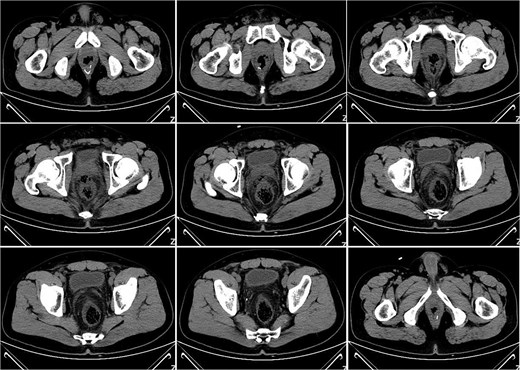

On postoperative Day 21, a follow-up pelvic CT scan indicated local gas accumulation around the rectum, suggesting an absorption phase of the infection (Fig. 4). By postoperative Day 28, a pelvic CT scan demonstrated minor gas accumulation at the anterior edge of the rectosigmoid junction, consistent with infection resolution and gas absorption in the surrounding area (Fig. 5). By postoperative Day 49, a pelvic CT scan revealed no abnormal density shadows in the perianal skin and soft tissues, with preserved fat planes (Fig. 6), indicating complete resolution of the perirectal infection and restoration of normal clinical status.